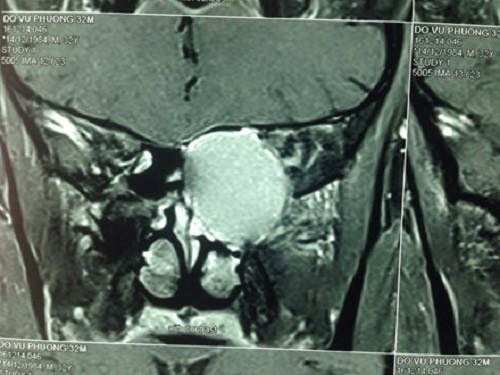

Chỉ còn vài hôm nữa sẽ đi cưới vợ nhưng chàng trai 32 tuổi bỗng dưng gần như bị mù do không điều trị. Các bác sĩ đã tiến hành phẫu thuật, sau một ngày mắt bệnh nhân đã nhìn thấy bình thường kịp chuẩn bị đám cưới.

Cứu chàng trai bỗng dưng bị mù trước ngày cưới ở Cà Mau